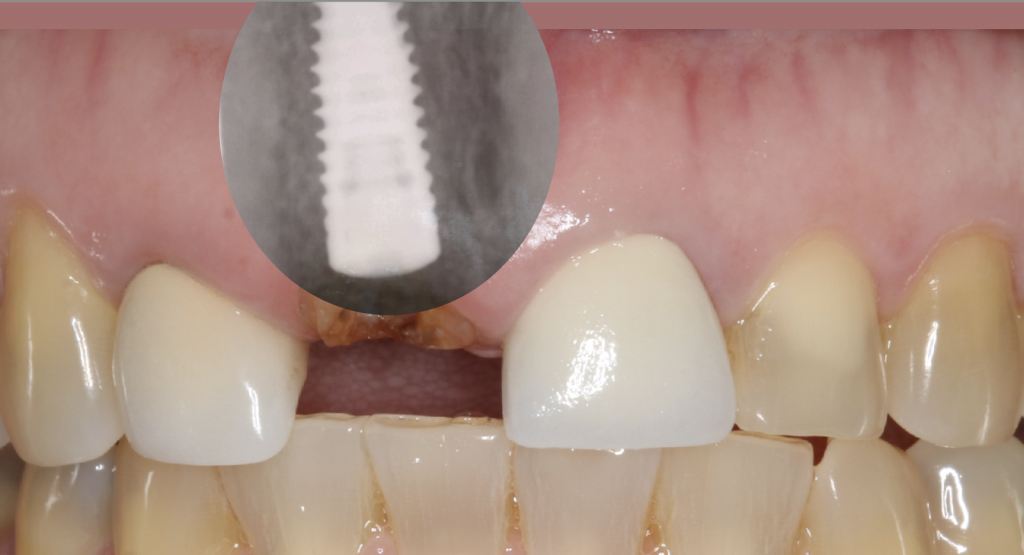

Dental implants have become the most desirable option to replace missing teeth due to their ability to integrate with our bodies and perform as natural teeth. The therapy requires careful study of the existing jawbone, and often times bone grafts are necessary to increase the bone volume to facilitate implant placement.